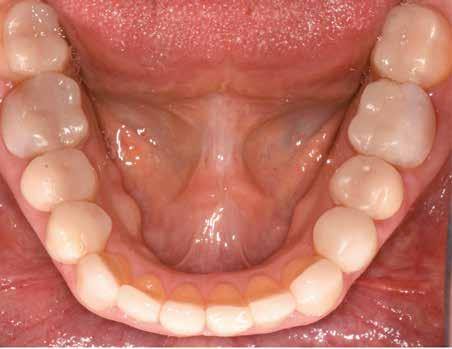

KOMPLEX FOGAZATI REHABILITÁCIÓ

A felnőtt páciensek kezelése során általában egyszerre több ellátásra szoruló elváltozást is diagnosztizálhatunk: hiányzó fogak, kopott fogazat, esetleg régi, nem megfelelő, sérült fogpótlások, rendellenes helyzetben lévő fogak stb… Ezen páciensek kezelésekkel kapcsolatos kérései mindig az esztétikai vagy a rágással kapcsolatos kívánságaik kielégítését szolgálja. A kezelések során a fogorvosoknak nem csak a páciensek kéréseinek teljesítésére, hanem ezzel egyidejűleg a fogazat általános megjelenésének és funkciójának lehetőség szerinti javítására is törekedniük kell. Mindemellett a lehető legtöbb saját foganyag megőrzését és az évek során elvesztett kemény- és lágyrészek pótlását (pl.: hiányzó fogak, sorvadt állcsontgerinc, lágyszöveti defektusok) is szem előtt kell tartaniuk, úgy, hogy közben egy hosszú távon fenntartható eredményekkel járó kezelési tervet állítanak össze. Ezek mindig összetett esetek. Annak érdekében, hogy a fentiekben megfogalmazott összes kezelési célt teljesíteni tudjuk, interdiszciplináris megközelítésre van szükség. Az ilyen komplex rehabilitációs kezeléseket „fogászati megfiatalításnak” nevezzük. Ezeknek a beavatkozásoknak lényege az elhasználódott fogazat biológiai szempontokat figyelembe vevő minimál invazív módon történő helyreállításában rejlik, mely folyamat végére a páciensek fogai visszanyerhetik fiatalkori megjelenésüket.

A rehabilitációs kezeléseknek a célja, hogy a páciensek a lehető leghosszabb időn keresztül képesek legyenek mosolyogni és rágni. A protetikai kezeléseket végző fogorvosoknak helyre kell tudni állítaniuk a fogívek szabályos lefutását és az alsó és felső fogív között megfelelő interokkluzális érintkezéseket kell létrehozniuk. Így lehet csak az ellátás befejezését követően elért végeredmény biológiai szempontokat figyelembe vevő esztétikáját, funkcionális megfelelőségét, hosszú távú fenntarthatóságát biztosítani.

A fogszabályzó kezelések egyik legfontosabb célja, hogy elérjük a lehető legharmonikusabb interokkluzális fogérintkezéseket, továbbá az állcsont relációs helyzetének frontális és szaggitális síkban is megfelelőnek kell lennie. A fogszabályzás befejezésekor a fogpozícióknak nem orthodonciai, hanem protetikai szempontok szerint kell ideálisnak lenniük. Az Invisalign ClinCheck szoftver (Align Technology) segítségével a protetikus az orthodontussal együtt meg tudja határozni azokat a végső fogpozíciókat, amelyek a lehető legjobb végeredmény biztosításához elengedhetetlenek. Bizonyos klinikai paramétereket, mint a fogak klinikai koronájának nagyságát, az egyes fogak fogíven belüli optimális pozícióját, a fogívek egymáshoz viszonyított helyzetét, a fogak között látható rések nagyságát, a frontfogak tengelyének dőlését, az overjet és overbite mértékét már a kezelések megkezdése előtt pontosan definiálni kell. Ezeket az adatokat viszont csak a tervezett végleges fogpótlás ismeretében lehet meghatározni, ezért van szükség az orthodontus és a protetikus szoros együttműködésére.